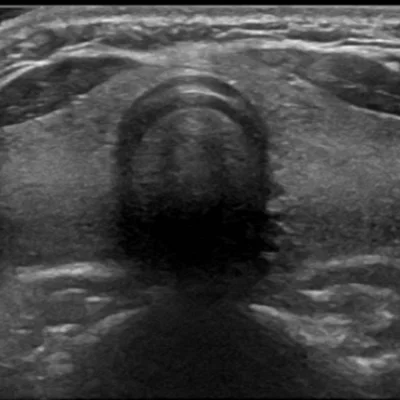

Small Parts Ultrasound

We provide targeted imaging for smaller anatomical regions

Thyroid

Detect nodules, goiters, or inflammation

Breast

Evaluate lumps, cysts, or post-mammography findings

Scrotum

Assess pain, swelling, or infertility-related issues

These scans are performed with precision and privacy, ensuring patient comfort and diagnostic accuracy.